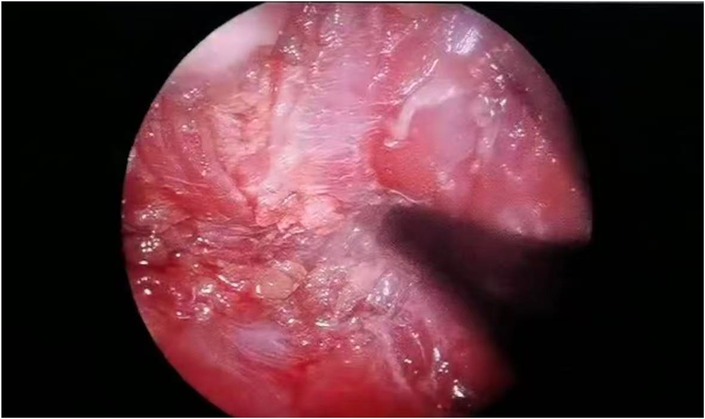

Endoscopic view showing a close-up of red and pink tissue with a textured surface and areas of shiny, reflective spots. The image depicts a medical examination of an internal body structure surrounded by a dark background.

Figure 5. Perforation and nerve injury were ruled out.